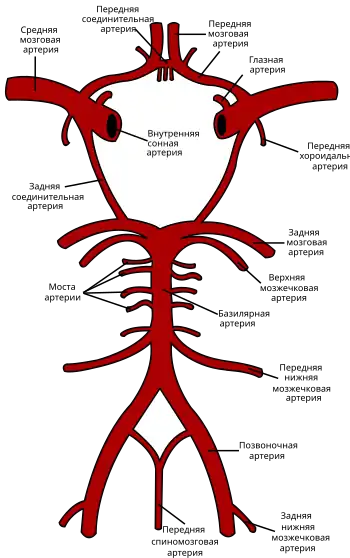

| Виллизиев круг | |

Базилярная артерия входит в состав Виллизиева круга — артериального круга, расположенного на основании головном мозге и отвечающего за кровоснабжение (в том числе и за хорошо развитое коллатеральное кровоснабжение) головного мозга кровью[1].

Виллизиев круг